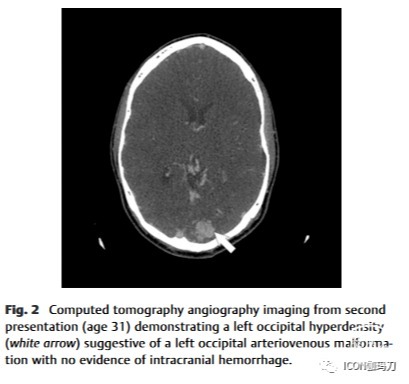

在初次就诊14年后,这位31岁的患者因癫痫发作时头部受伤而向急诊科报告。头部CT血管造影显示左侧枕叶内1.9 × 1.4 cm高衰减血管团块(图2),无出血迹象。脑血管造影证实存在未破裂的2.9 cm的 Spetzler-Martin 3级左枕部AVM(图3)。AVM由大脑后动脉的胼胝体支和颞后支供血,并有浅静脉引流和深静脉引流。该枕部AVM在当时的MR成像上也得到了证实(图1D-F)。

图2第二例患者(31岁)的ct血管造影显示左侧枕部高密度(白色箭头),提示左侧枕部动静脉畸形,无颅内出血迹象。